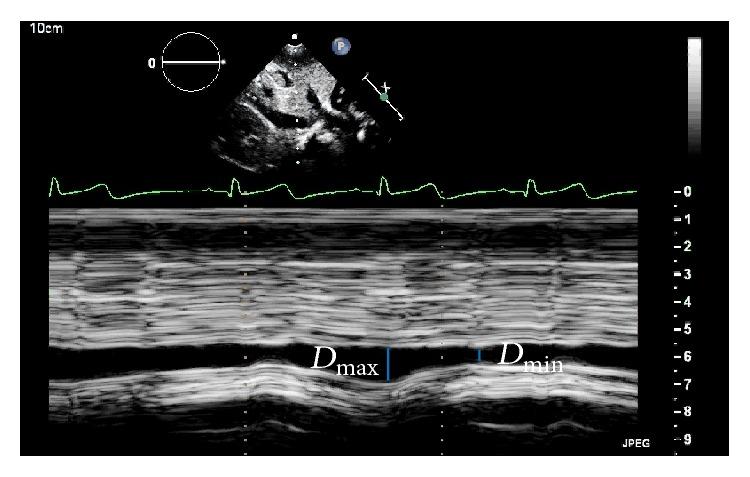

Echocardiography is a key tool for hemodynamic assessment in Intensive Care Units (ICU). Focused echocardiography performed by nonspecialist physicians has a limited scope, and the most relevant parameters assessed by focused echocardiography in Pediatric ICU are left ventricular systolic function, fluid responsiveness, cardiac tamponade and pulmonary hypertension. Proper ability building of pediatric emergency care physicians and intensivists to perform focused echocardiography is feasible and provides improved care of severely ill children and thus should be encouraged.

超声心动图是重症监护病房(ICU)血流动力学评估的关键工具。由非专科医生进行的床旁超声心动图检查范围有限,小儿重症监护病房中通过床旁超声心动图评估的最相关参数是左心室收缩功能、液体反应性、心包填塞和肺动脉高压。对儿科急救医生和重症监护医生进行床旁超声心动图检查的适当能力培养是可行的,并且能改善对重症患儿的护理,因此应予以鼓励。